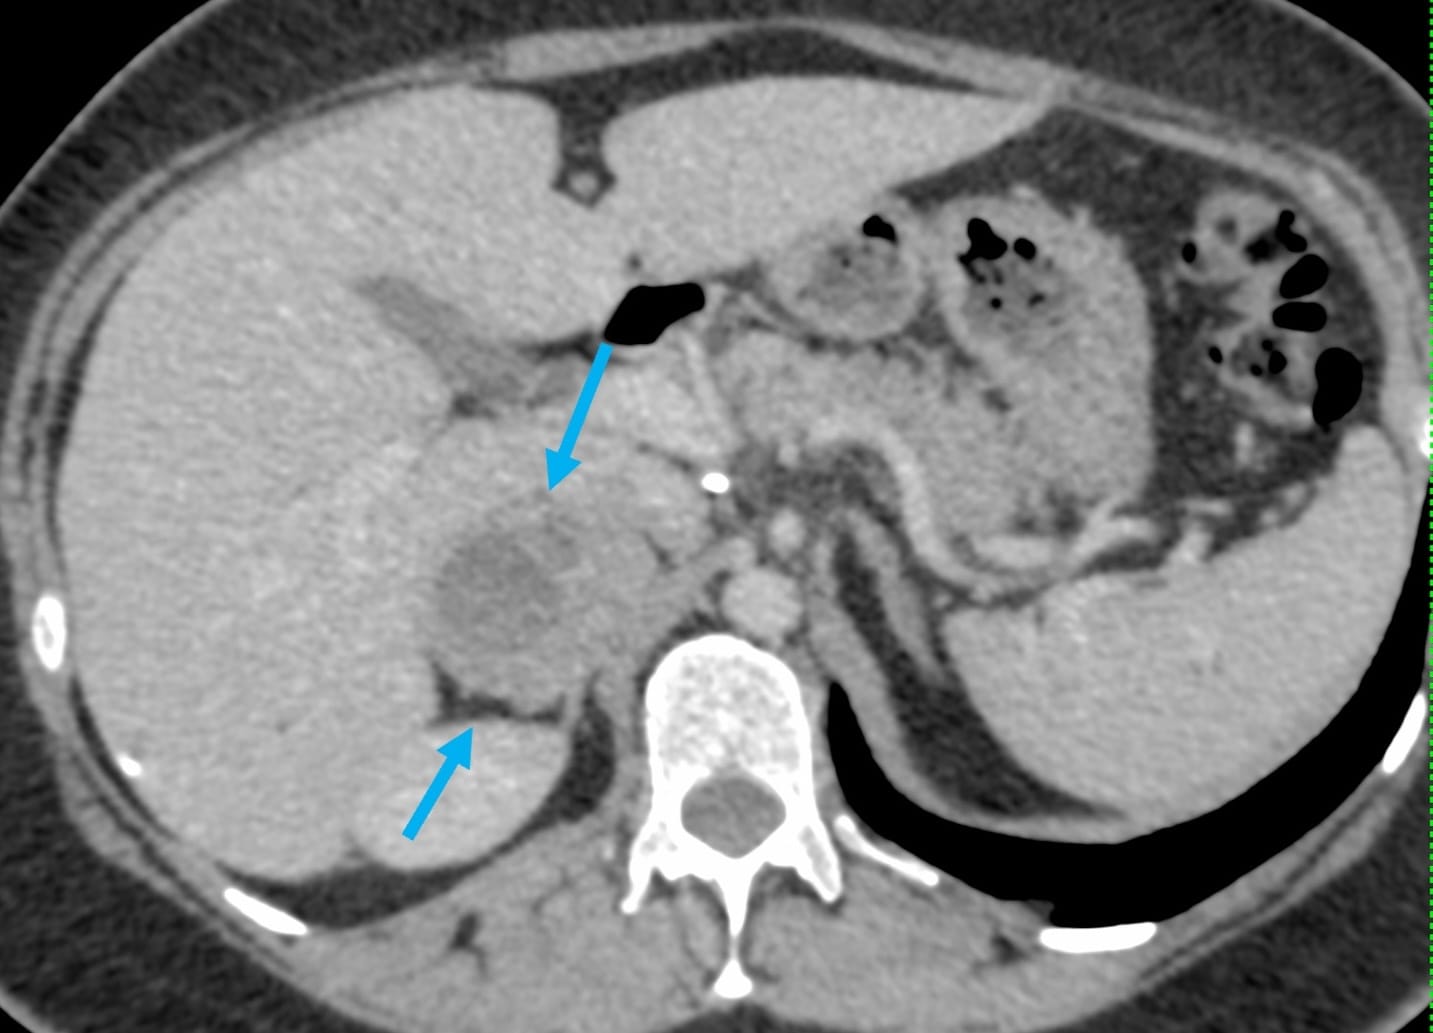

A 40-yrs old presented with a right adrenal gland nodule for biopsy.

What route will you take?